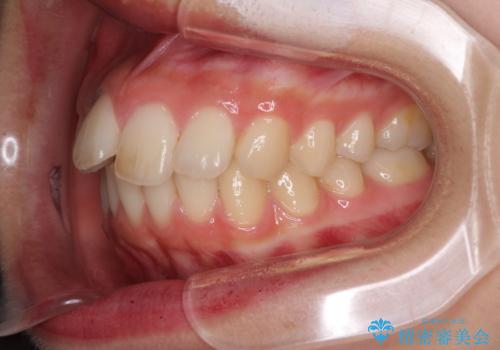

就職前にきれいな歯並びにしたい 大学生のインビザライン矯正

- 就職するまでに歯並びをきれいにしたいとのことで来院された患者様です。

前歯の叢生を気にしていましたが、極力突出感を改善できるようにすることとし、インビザラインにて矯正治療を行うこととしました。

改善の期待できない口元の突出感改善を希望されたため、いたずらに治療期間が延びましたが、きっちりと仕上がりました。